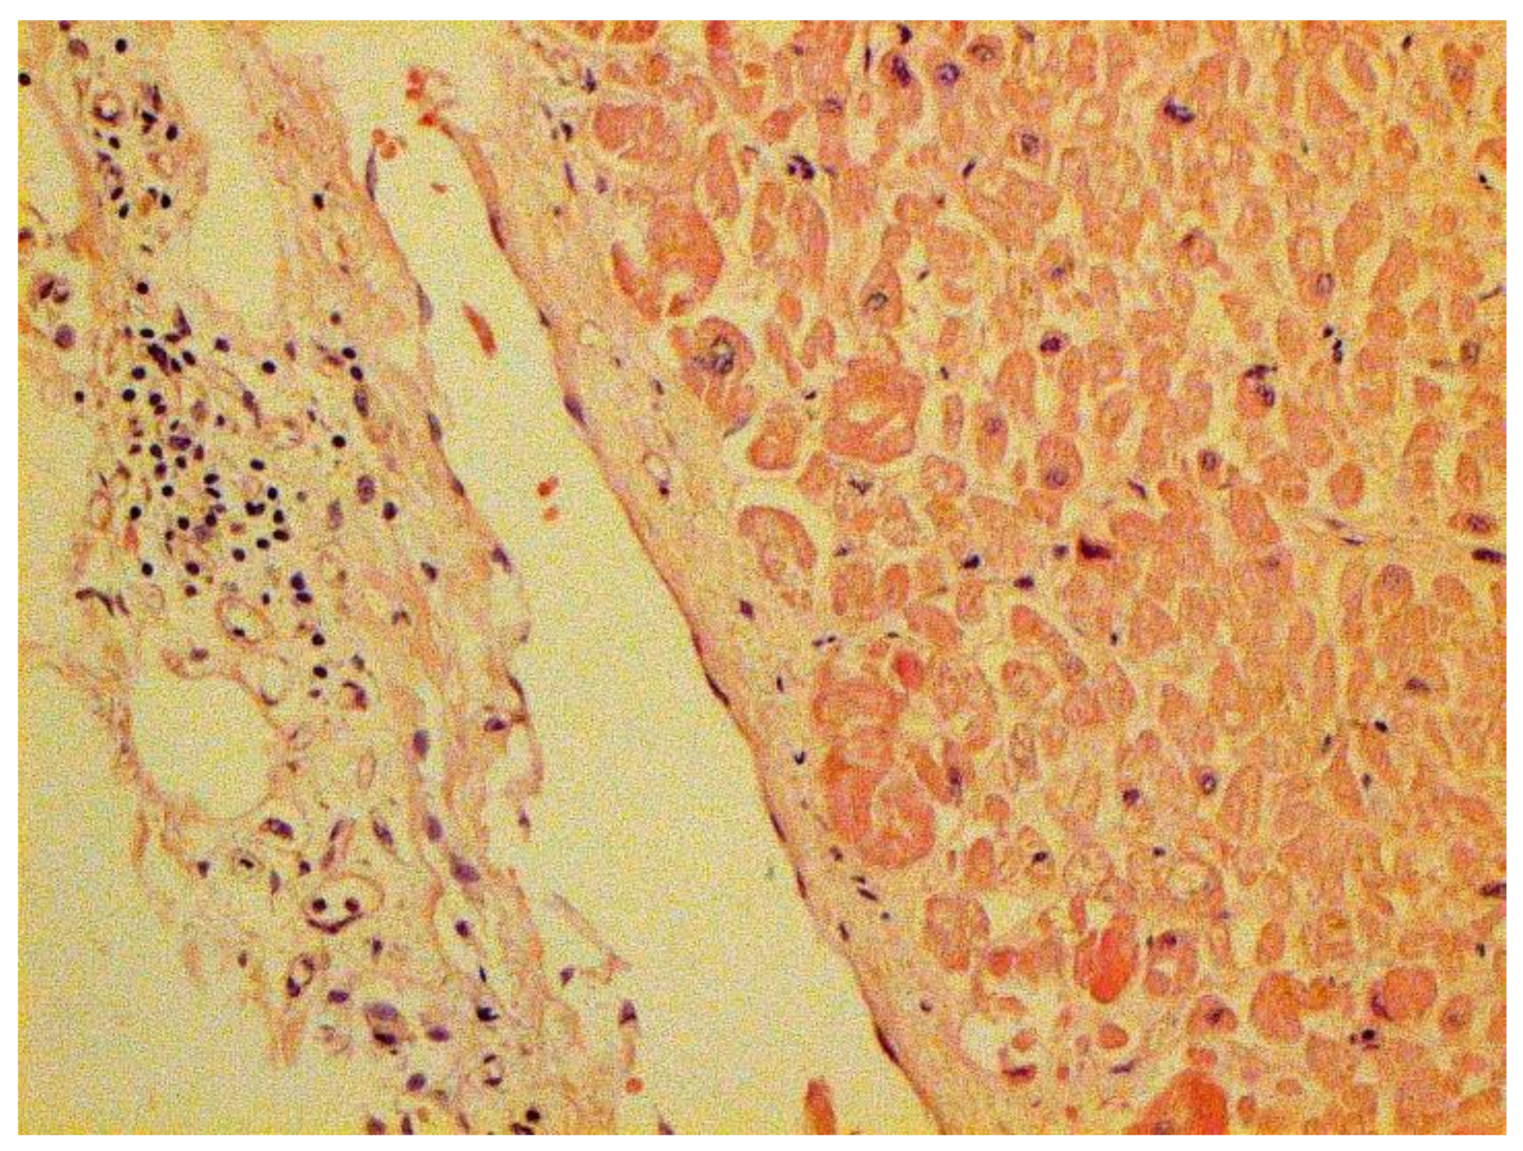

The hallmarks of apoptosis (according to expression of caspase-3) were revealed in the lungs, lymph nodules, and other organs, predominantly in the area with the small granular rhexis (Figure 4 and Figure 5.) The possibility of developing a generalized infection with damage to other organs is evident. Alterative and necrotic changes were seen in parenchymal cells. Sometimes we noted their changes in the nuclei of the cells in the lymph nodes, intestines, soft meninges, heart, pancreas, kidneys, and spleen. We succeeded in detecting spike and nuclear antigen of the virus in the lymph nodes (Figure 6), pancreas, brain (Figure 7), and adrenals. We described certain lesions in the adrenals that are probably associated with the SARS-CoV-2 virus [25].

In many vessels, we also observe thrombi in different vessels (Figure 16 and Figure 17). We succeeded in detecting virus spike antigen in endothelial cells as well as in other layers of vascular walls. The formation of fibrin thrombi in blood vessels (probably DIC) and infiltration by T lymphocytes, including cytotoxic cells (Figure 18 and Figure 19), were seen not only in the parenchyma of the organs but in the surrounding tissues as well. It is important to compare the localization of virus antigens and cytotoxic CD8+ cells (Figure 20).

Figure 18. Infiltration of adrenal by CD3+ lymphocytes. IHC ×100.

Figure 19. Infiltration of pericardium by CD8+ lymphocytes. IHC ×100.